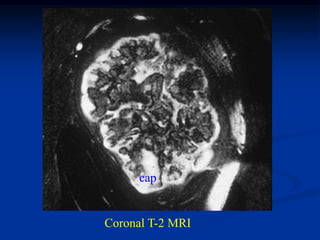

Coronal T-2 MRI

cap